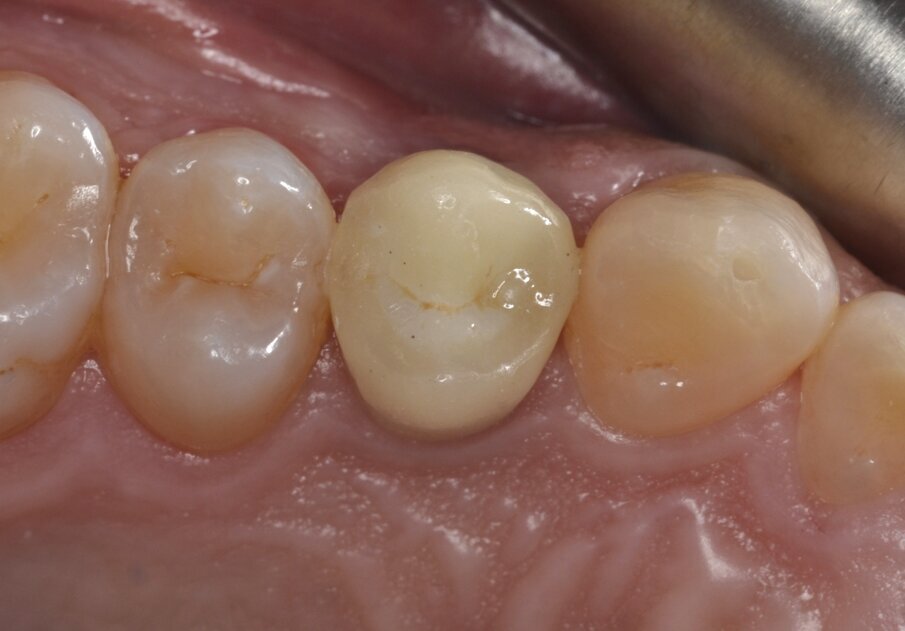

All’esame obiettivo viene si evidenzia una frattura verticale a carico dell’elemento in questione (Figg. 1, 2) che pone indicazione assoluta all’estrazione dentaria; per evitare di aggravare l’inevitabile contrazione della cresta ossea alveolare, si decide di eseguire l’estrazione dell’elemento fratturato senza sollevare alcun lembo. Viene effettuato un esame radiografico endorale allo scopo di visualizzare la morfologia della radice dentaria e i suoi rapporti con le strutture viciniori. (Fig. 3)

Fig. 1 - Elemento 1.4 fratturato (visione occlusale).

Fig. 2 - Elemento 1.4 fratturato (visione buccale).